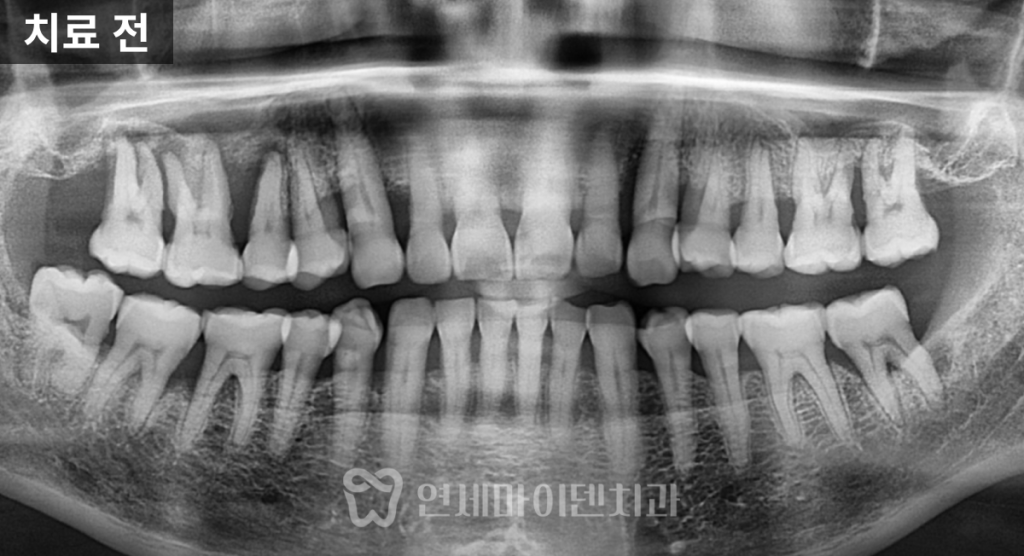

방사선 사진을 확인해보니

치아 주변 잇몸뼈가 상당 부분 녹아 있었고,

치아는 고정력을 거의 잃은 상태였습니다.